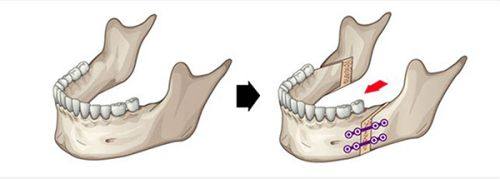

2. 地包天矫正:地包天会导致面部不协调,影响患者的自信心。尹泰镐院长能够正确判断地包天的成因和类型,采用合适的矫正方法。对于牙性地包天,他可以通过牙齿矫正来调整牙齿的咬合关系;对于骨性地包天,则可能需要进行手术治疗。他的矫正方案能够较大程度地修复患者正常的咬合功能和面部形态。